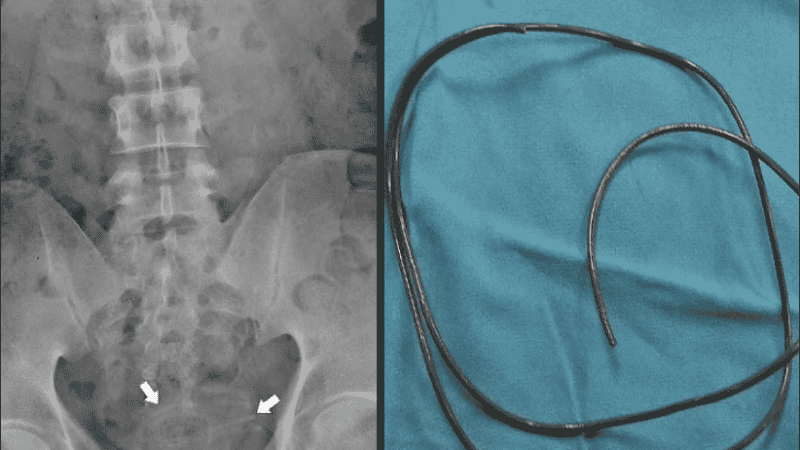

Los médicos lo describieron como "alojado en la vejiga". Le hicieron una radiografía para ver qué tan adentro de su cuerpo y cuánto daño había causado. Era 'visible y rápidamente identificado'.

El cable, que tenía alrededor de 3 mm de ancho, estaba enrollado pero, afortunadamente para él, no se había adherido a la pared de la vejiga. Si se hubiera alojado, los urólogos afirman que podría haber causado un agujero que necesitaba cirugía para repararlo. Los médicos lo sacaron con unas pinzas, aunque no está claro si quedó algo del cable colgando para agarrarlo. El hombre pasó la noche en el hospital para ver si necesitaba más tratamiento. Fue dado de alta al día siguiente.